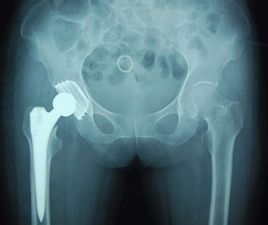

股骨頸骨折是髖部最常見的損傷,在全身骨折中其發病僅次於撓骨遠端骨折。這種骨折多因走路不小心跌倒,臀部著地而引起,傷後髖部疼痛,不能站立和行走。年輕人的股骨頸骨折多因車禍或高處摔傷等強烈暴力引起。股骨頸骨折的大多數有比較明顯的移位,且因為這個部位的槓桿作用較大,骨折不穩定,因此,多數需要手術治療。

股骨頸骨折手術後一般要闖三關:

一是術後感染關,這一關多數患者能闖過,一般是10天左右;

二是癒合關,股骨頸部位血運差,大多患者為中老年人,困此癒合起來較為緩慢,一般需要3個月至1年左右,年齡越大癒合越難,不癒合率大約可以達到30%左右。前兩關作為醫生和患者來講,都比較重視。

第三關是股骨頭壞死關,這一關往往容易被忽視。臨床常見的情況是:股骨頸骨折手術後復位、內固定、癒合都很順利,醫生患者都很滿意,於是不作保護、隨意活動,最終造成股骨頭壞死,留下終身遺憾。